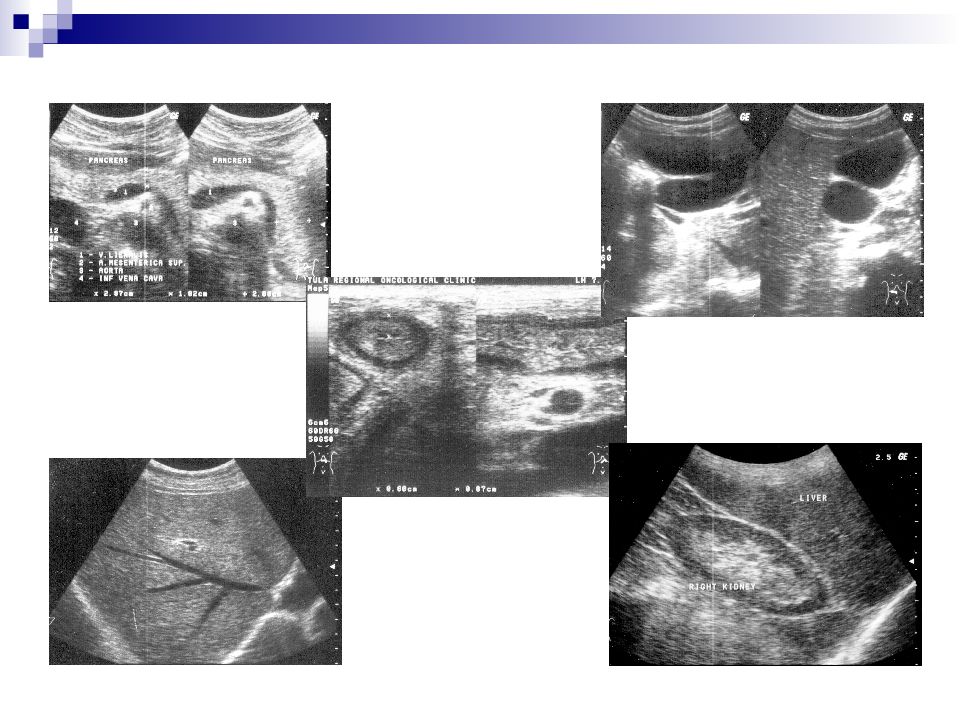

Слайд 25: Общие ультразвуковые исследования

Печени и желчного пузыря. Поджелудочной железы. Селезенки. Почек. Мочевого пузыря (в т.ч. с определением количества остаточной мочи). Органов малого таза (в т.ч. вагинальным датчиком). Плода. Предстательной железы (трансректально). Зон расположения внутрибрюшных и забрюшинных лимфоузлов. Внеорганных образований брюшной полости и забрюшинного пространства.

Слайд 26: Общие ультразвуковые исследования

Брюшной полости - печени и желчного пузыря, - поджелудочной железы, - селезенки, - зон расположения внутрибрюшных и забрюшинных лимфоузлов, - внеорганных образований брюшной полости и забрюшинного пространства, - полых органов на предмет наличия участков утолщения стенок.

Слайд 27: Общие ультразвуковые исследования

Молочных желез. Щитовидной железы. Периферических лимфоузлов. Мягких тканей.